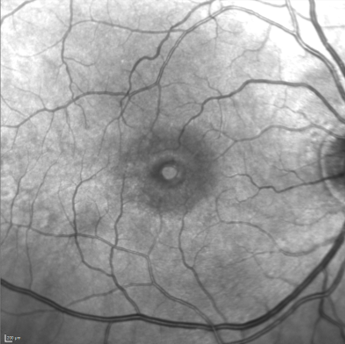

Rétinophoto 35° en infrarouge montrant un trou maculaire